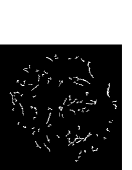

III-C Postprocessing

Since some non-vessel regions may still exist in the final segmented vessel image Ivsubscript𝐼𝑣I_{v}, the regions whose Area<a2𝐴𝑟𝑒𝑎subscript𝑎2Area<a_{2} && Extensibility>e2𝐸𝑥𝑡𝑒𝑛𝑠𝑖𝑏𝑖𝑙𝑖𝑡𝑦subscript𝑒2Extensibility>e_{2} && VRatio<r𝑉𝑅𝑎𝑡𝑖𝑜𝑟VRatio<r in Ivsubscript𝐼𝑣I_{v} are abandoned to remove these non-vessel regions.